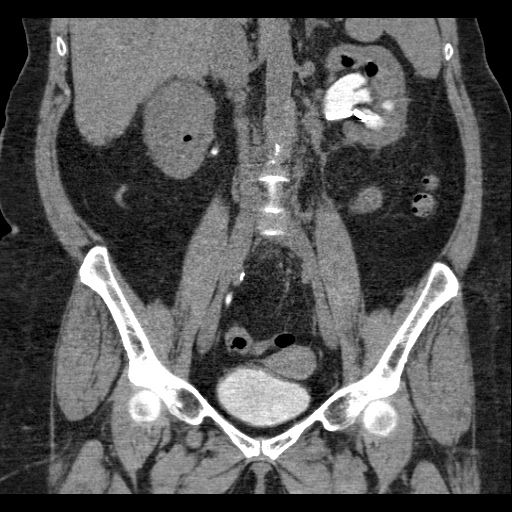

КТ-исследование абсцесса малого таза: Визуализация и диагностика

Раздел: Фотоальбом решений